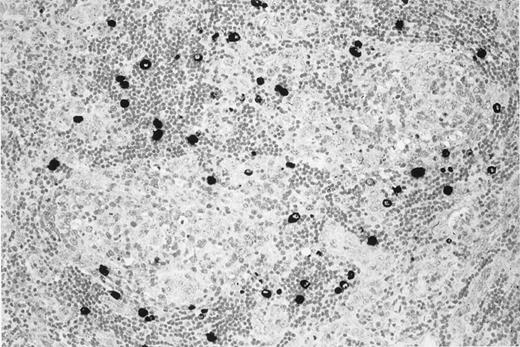

On November 26, 1997, a 52-year-old woman with HIV-1 infection came to the emergency department because of a 2-week history of progressive fatigue, high-grade fever (39°C), profuse sweating, and dyspnea. She had acquired HIV infection 4 years earlier through sexual contact. The absolute number of CD4+ T cells was 383 cells/μL, and HIV-1 viral load in plasma was less than 500 copies/mL. She was receiving antiretroviral therapy with d4T and 3TC. Generalized lymphadenopathy and splenomegaly were evident on physical examination. Chest radiography findings were normal. Her hemoglobin concentration was 7 g/dL. C-reactive protein (CRP) concentration was 4.8 mg/dL, and lactic dehydrogenase (LDH) level was 893 IU/L. She had hemolytic anemia, positive Coombs test findings, and evidence of cryoagglutinins. A latero-cervical lymph node was excised. Microscopic examination and immunohistochemistry for KSHV v–IL-6 revealed KSHV-related MCD (Figure1).

KSHV v–IL-6 expression in a lymph node of the patient with multicentric Castleman disease.

MCD lymph node section showing KSHV v–IL-6 expression (black) restricted to lymphocytes in the mantle zone of lymphoid follicles.